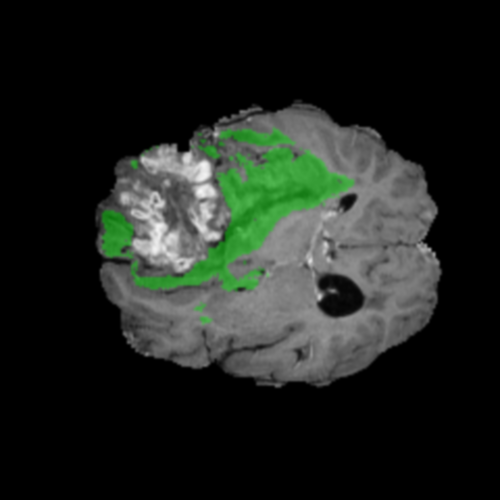

Mapas de Explicabilidad (Grad-CAM++)

Visualización de las regiones de atención del modelo que validan su razonamiento clínicamente relevante

Ejemplos HGG - Atención en Núcleo Necrótico y Tumor Realzado

HGG Grad-CAM++ 1 HGG Grad-CAM++ 2 HGG Grad-CAM++ 3 HGG Grad-CAM++ 4 HGG Grad-CAM++ 5 HGG Grad-CAM++ 6

Los heatmaps muestran que el modelo concentra su atención en las regiones de Tumor Realzado (rojo) y Núcleo Necrótico (azul), características patológicas clave de los gliomas de alto grado.

Ejemplos LGG - Atención Difusa en Edema Peritumoral

LGG Grad-CAM++ 1 LGG Grad-CAM++ 2 LGG Grad-CAM++ 3 LGG Grad-CAM++ 4 LGG Grad-CAM++ 5 LGG Grad-CAM++ 6

Para casos LGG, la atención del modelo es más difusa y se concentra principalmente en la región de Edema Peritumoral (verde), consistente con la naturaleza más infiltrativa y menos agresiva de estos tumores.

Validación con IA Explicable

El análisis Grad-CAM++ reveló que el modelo desarrolla automáticamente la capacidad de localizar las regiones tumorales. Para casos HGG, la atención se alinea fuertemente con las regiones de Tumor Realzado (ET) y Núcleo Necrótico (NCR). En contraste, los casos LGG muestran atención más difusa, principalmente concentrada en la región de Edema Peritumoral (ED), lo cual es consistente con la patofisiología conocida de los gliomas.

✅ Validación con IA Explicable